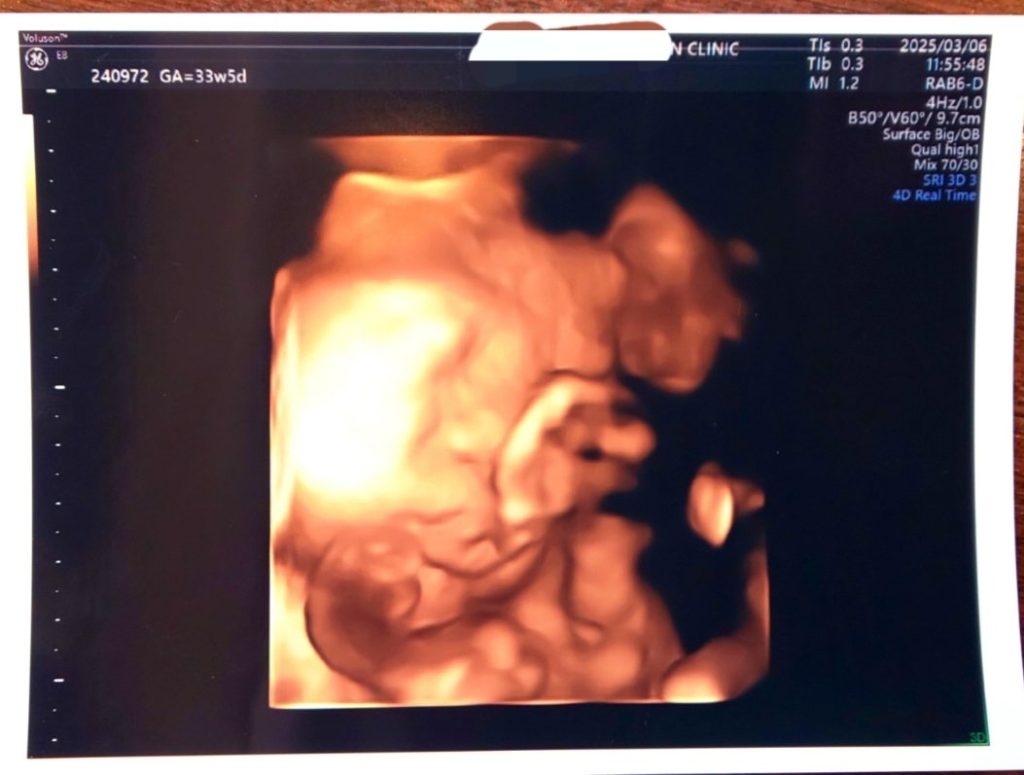

3/6 33w5d 推定体重2,100g

いちおう顔らしいですがうちの子、顔を見せてくれなかったり背中向けてたりでいつも写真映りが悪い…笑 先生が頑張って写りのいいところ探してくれましたが顔を埋めている状態だったので断念。推定体重2100g!1ヵ月前の2/7よりも+600g、そりゃお腹重いわ…